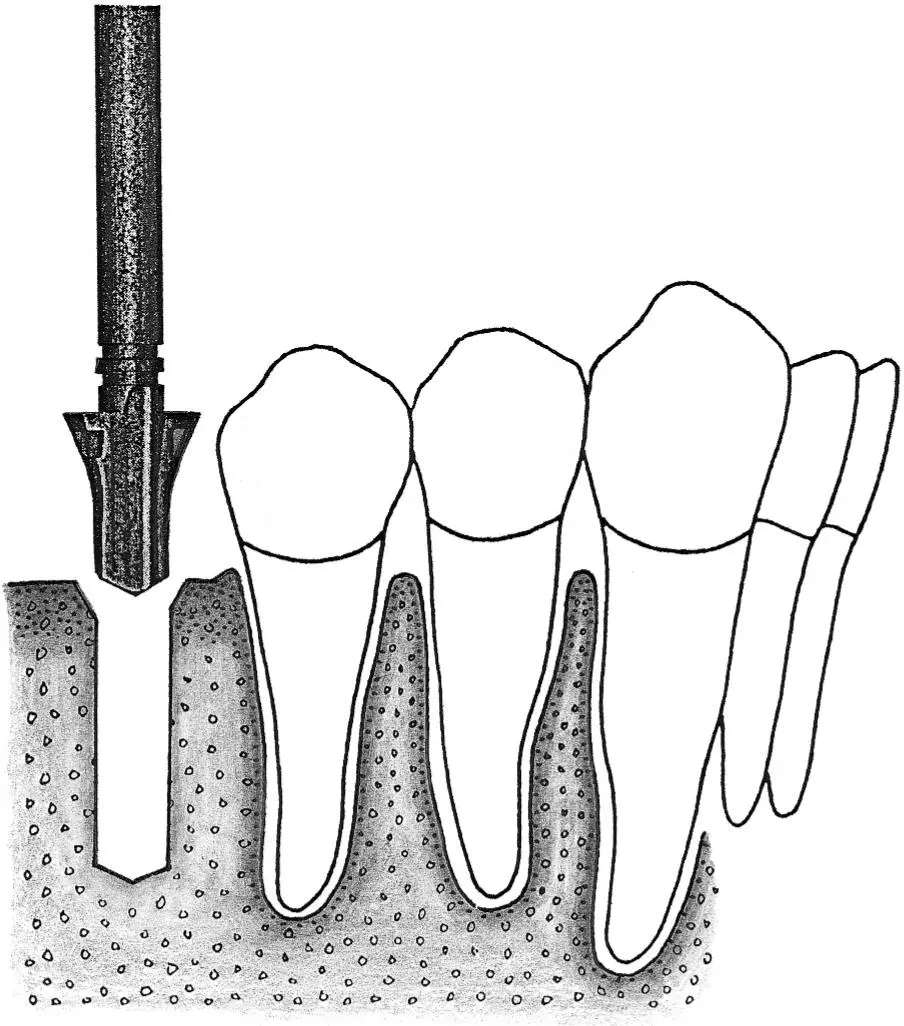

Fig 1-2Sequence of site preparation for a standard implant.

Fig 1-2e The crest of the osteotomy is enlarged with a no. 3 round bur.

Fig 1-2f A 2.8-mm-diameter spiral drill is easily inserted for preparing the depth of the site.

Fig 1-2g A profile drill is used to further increase the surgical access for the next, larger-size drill.

Fig 1-2h Preparation of the implant site continues with the 3.5-mm-diameter spiral drill.